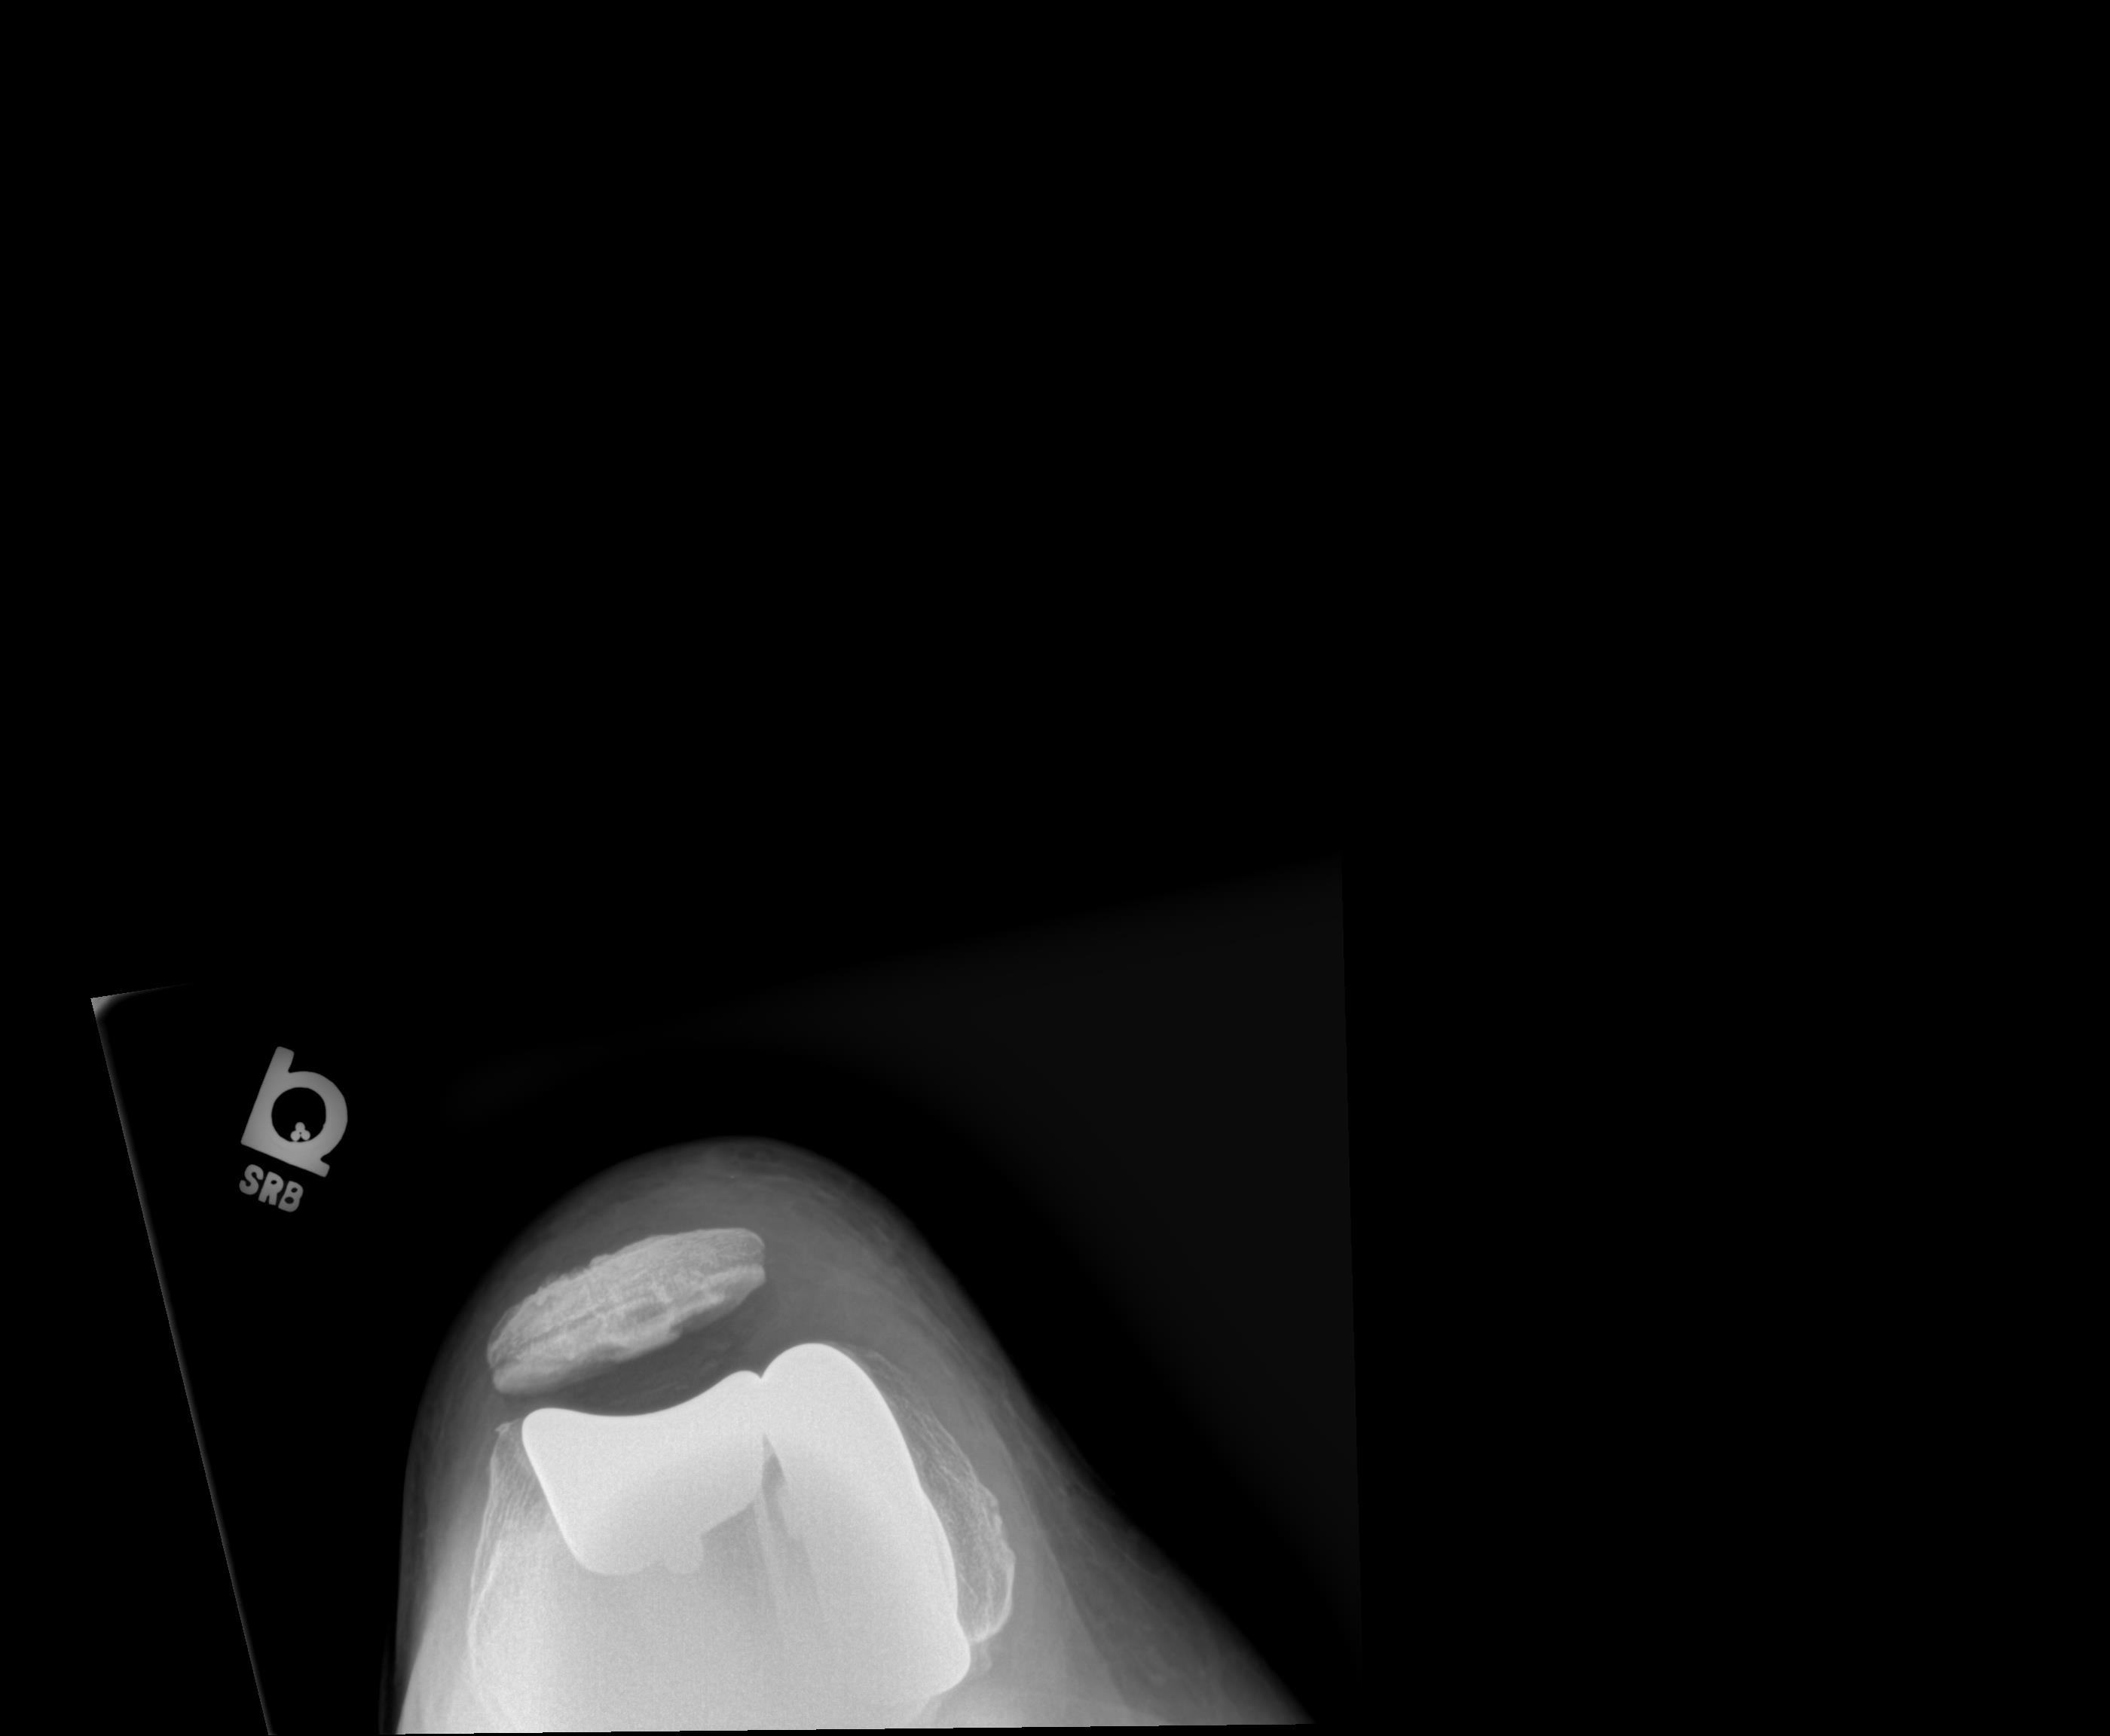

After – Left Knee Cap

Before - Right Knee

After - Left Knee